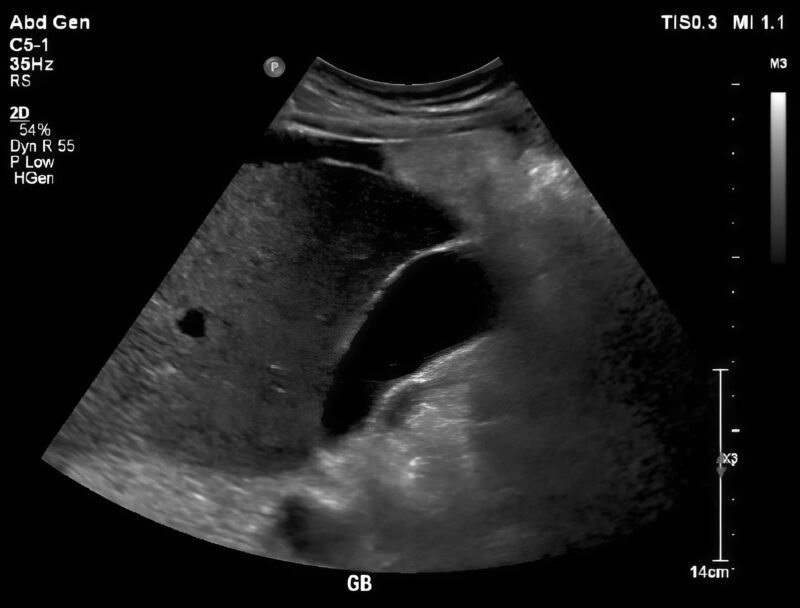

A doctor arrived quickly, calm but focused. He pressed gently on my abdomen, and I cried out despite trying to stay composed. After blood tests and an urgent ultrasound, he returned with a look that was serious—but not panicked.

Gallstones.

Tiny, hardened stones had formed inside my gallbladder, blocking the bile duct and causing severe inflammation. One stone had become lodged in exactly the wrong place, triggering the unbearable pain and constant vomiting. If left untreated, it could lead to infection, rupture, or even sepsis. The pain wasn’t random—it was my body screaming for help. ⚠️🩺